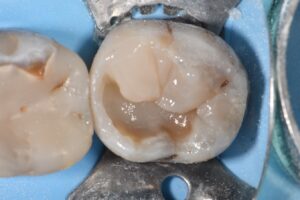

(Afternoon tea pics 2224.9: Rhondium DME wedge | Garrison Wide Prep Ring)

Two pieces of kit that are indispensable for extensive Class II composite restorations where the line angles are missing.

Restorative: Kerr Simplishade Dark | Simplishade Bulk Fill flowable